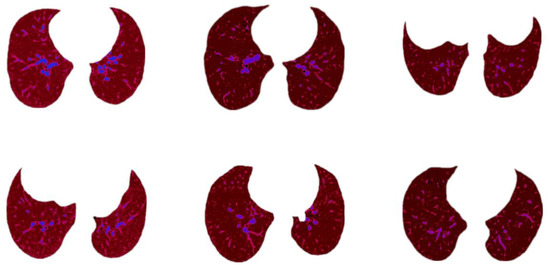

A total of 17,104 lung CT scan images provided by Kaggle were analyzed for this research [23]. The dataset was divided into three classes named Non-COVID, COVID, and CAP, where 6983 lung CT images are Non-COVID, 7593 images are COVID, and 2618 are CAP. The images have a 512 × 512 pixel size. A description of the dataset is given in Table 1.

A sample image of each corresponding class is illustrated in Figure 1.

Figure 1. CT images of the three classes of the dataset.